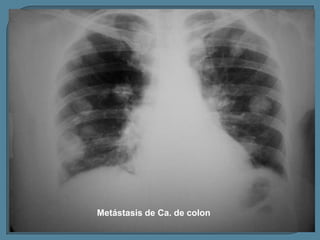

Metástasis de Ca. de colon